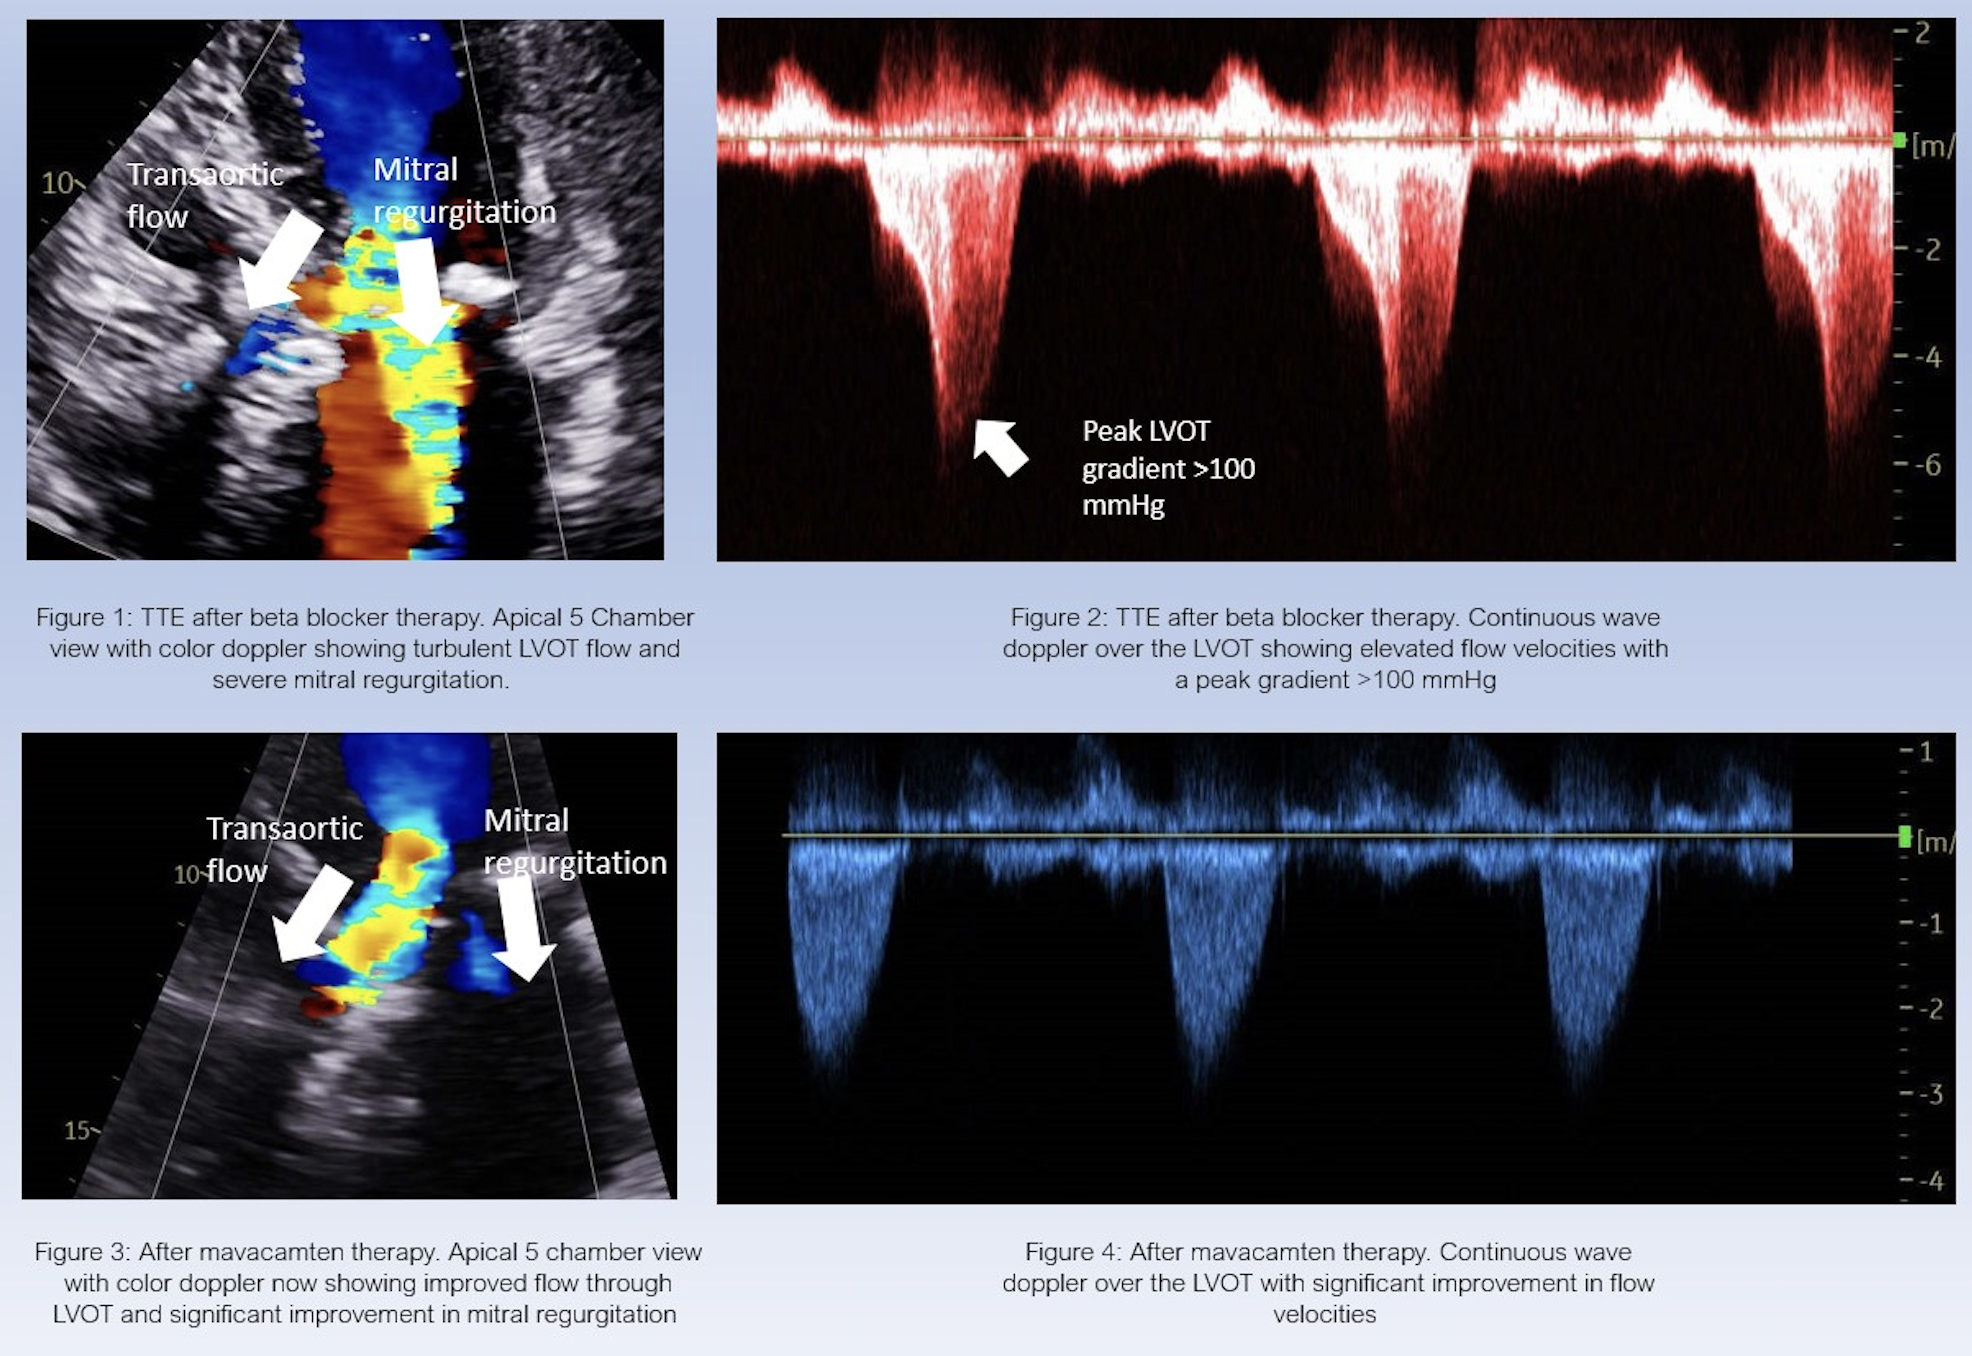

A 76 year old female with a past medical history of hypertension, severe aortic stenosis, and coronary artery disease underwent a Medtronic Evolut TAVR in March 2022. Her TTE post TAVR showed LVOT peak gradient greater than 100 mm Hg, LVEF 75% and severe eccentric mitral regurgitation secondary to systolic anterior motion (SAM) of the mitral valve (MV). After multidisciplinary discussion, the patient was discharged on maximally tolerated BB therapy. Follow up TTE showed persistent obstruction and gradients, so diltiazem was added to her regimen. Her subsequent TTE showed a peak LVOT > 100 mmHg at rest, and severe MR. Given persistent findings, she was started on mavacamten, continued on metoprolol, and tapered off of diltiazem. Her TTE two months after initiation of mavacamten revealed resolution of LVOT gradients, reduction of MR to mild and normal LV and TAVR function. She tolerated the therapy well and endorsed ongoing symptomatic improvement on subsequent follow up.

With the increasing use of TAVR therapy, there has been a corresponding rise in cases of post-TAVR obstruction that must be managed. As demonstrated by this case, management with BB therapy alone may be suboptimal. Although mavacamten is currently approved in patients with HCM, the obstruction in post-TAVR patients is functionally similar. Thus, this medication was trialed as a supplemental treatment in this patient and yielded positive results. This case highlights the potential benefit of extending use of mavacamten alongside β-blocker therapy for this patient population and suggests the need for future studies.